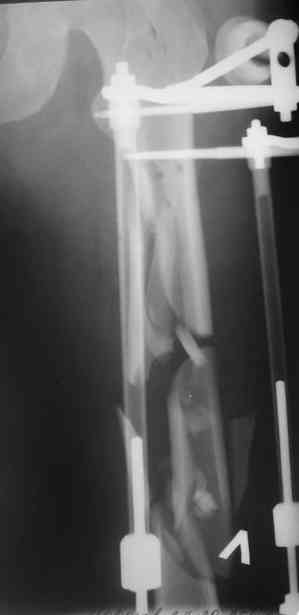

А в чем проблемы? Пример в приложении.

Насчет снимка Вами представленного - смотрится оч красиво, еще бы на функцию узнать...

В приложении функциональные снимки в 3 мес. и в 1 год.